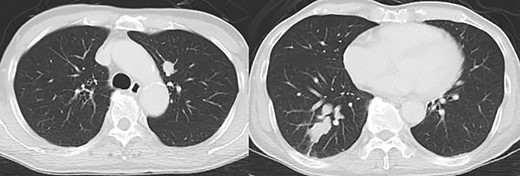

Contrast-enhanced computed tomography revealed a giant irregular mass (45 × 35 mm) in the abdominal wall (Fig. 2). No other intra-abdominal neoplasm were present; however, an irregular lung mass measuring 50 mm in size in the S10 region of the right lobe and a mass measuring 12 mm in size in the S1/2 region of the left lobe were found (Fig. 3). Total gastrointestinal endoscopy, including capsule endoscopy, revealed no neoplasm in the intestinal tract (Fig. 4a–c).